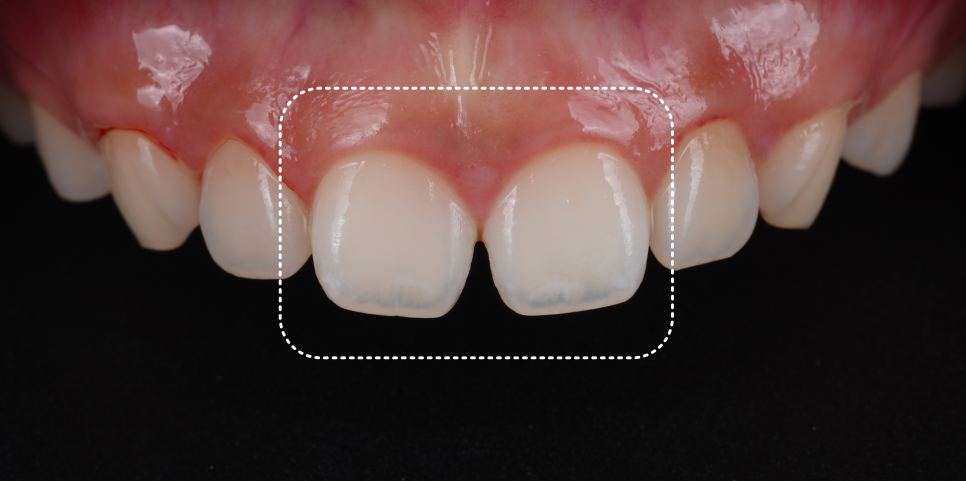

구강 내를 보면, 앞니가 살짝 항아리 모양으로 윗부분은 정상적이지만 끝으로 갈수록 좁아져 벌어져 보이는 형태였죠.

이런 모양은 치아가 움직이지 않아도 빛이 통과할 때 자연스럽게 틈이 더 도드라져 보이게 만들어요.

그래서 이런 경우는 교정으로도 해결이 안 되고, 치아 형태를 다시 디자인해야 합니다.

촬영 : 251030